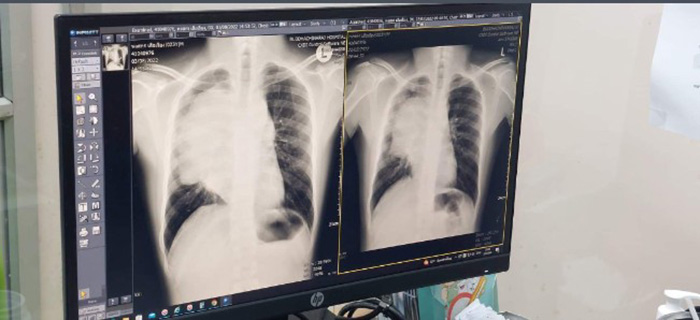

เรื่องมันมีอยู่ว่า เราเริ่มทำไรเหนื่อยง่าย นอนราบไม่ได้ เพราะหายใจไม่ออก ทำไรนิดอะไรหน่อยก็หอบเป็นหมาล่ะ ได้ไปเอกซเรย์กับรถเคลื่อนที่พบว่ามีก้อนที่ปอด เลยไปตรวจที่โรงพยาบาลเพื่อความแน่ใจ ซึ่งก้อนดังกล่าวนั้น เป็นก้อนที่โตเร็วและไม่เจ็บ ก็เลยเจาะชิ้นเนื้อไปตรวจ มีก้อนขนาดเส้นผ่านศูนย์กลาง 15 เซนติเมตร อยู่ในช่องทรวงอกของเรา อยู่ระหว่างปอด 1 ข้าง ใกล้ ๆ กับหัวใจและพวงเส้นเลือดใหญ่ต่าง ๆ ที่รับเลือดเสียกลับเข้าหัวใจ และส่งเลือดดีออกไปเลี้ยงร่างกาย

โดยหลังจากที่อาจารย์หมอเห็นผล CT scan พบว่าก้อนมะเร็งนั้นโตจนไปกดเส้นเลือดใหญ่ ไม่ถึงสัปดาห์ก็มีอาการหน้าบวม แขนบวม หายใจไม่ออก หลังจากนั้น 6 เดือนผ่านไป คุณก้อนก็ทำให้เราได้พักผ่อน อยู่บ้านอย่างระมัดระวัง ไปรับยาเคมีบำบัดตามรอบ มีหน้าที่อย่างเดียว คือห้ามติดเชื้อใด ๆ เด็ดขาด รับยาเคมีบำบัดให้ครบตรงเวลา และที่ทุกคนของ่าย ๆ อย่าตาย